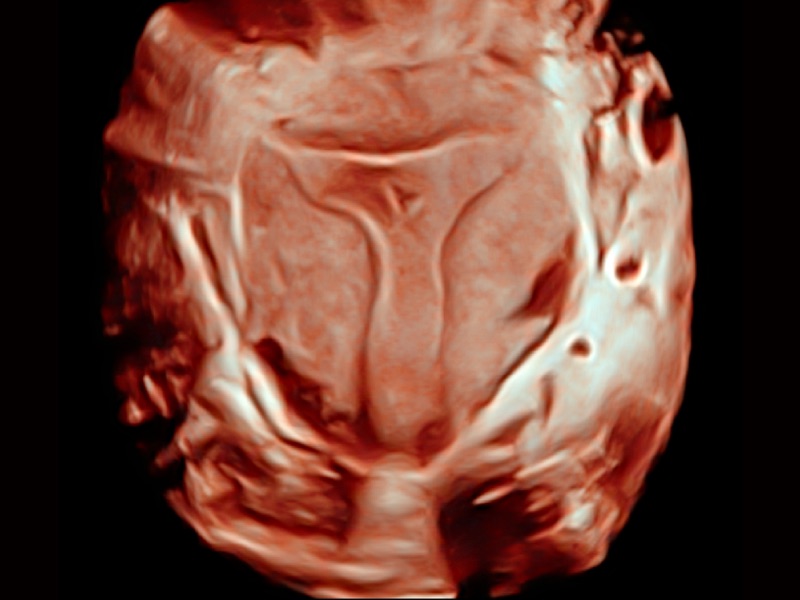

心血管应用

三维光影成像技术采用新型的渲染方式,增强边缘信息,使得轮显示清晰完整,为临床提供丰富、直观的三维结构,提供临床诊断准确性。

通过心肌识别技术和二维斑点追踪技术相结合,计算心肌各节段的应变应变率、速度、位移并以曲线图显示,实现整体或者局部心肌定量分析。同时可呈现牛眼图直观和准确诊断心肌的运动情况。